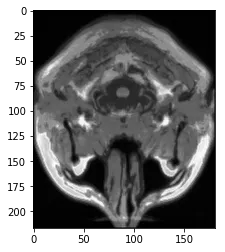

brains,形状为(10, 181, 217, 181)。每个脑由181个z平面沿着z轴(通过头顶到颈部)组成,其中每个切片在x(耳朵到耳朵)和y(眼睛到后脑)平面分别为181个像素和217个像素。所有的脑都是

dtype('float64')类型。所有脑中的最大像素强度为~1328,最小值为~0。例如,对于第一个脑,我通过brains[0].max()计算得到1328.338086605072,brains[0].min()计算得到0.0003886114541273855。下面是brain[0]切片的绘图: